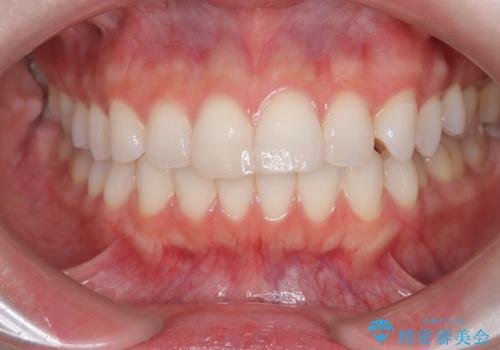

歯の中心のズレを解消し、より美しい口元へ